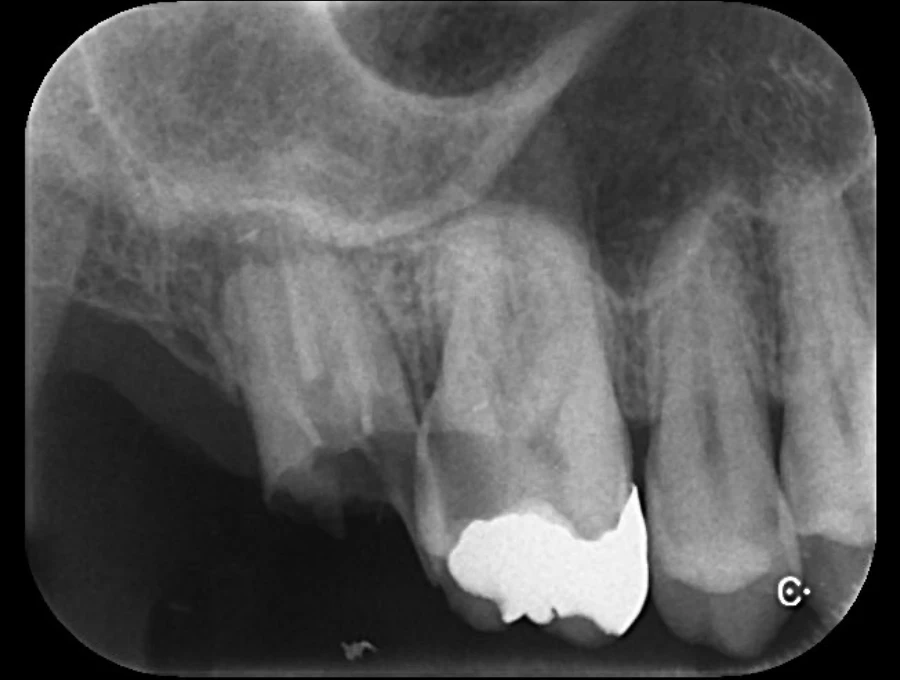

Case.01

治療前

治療後

| 主訴 | 虫歯を治したい。白く強度のあるものにしたい。 |

| 治療期間 | 1か月(3回) |

| 治療費 | 1本 ¥80,000+税 |

| 治療内容 | 右上4,5,6番目の虫歯を除去し、セラミックインレーを装着しました。 |

| 治療のリスク | 神経を温存しています。一時的に知覚過敏の症状が出ることがあります。また、咬合の強い方の場合、材料の破損の恐れがあり、夜間のマウスピースの装着をお勧めしております。 |